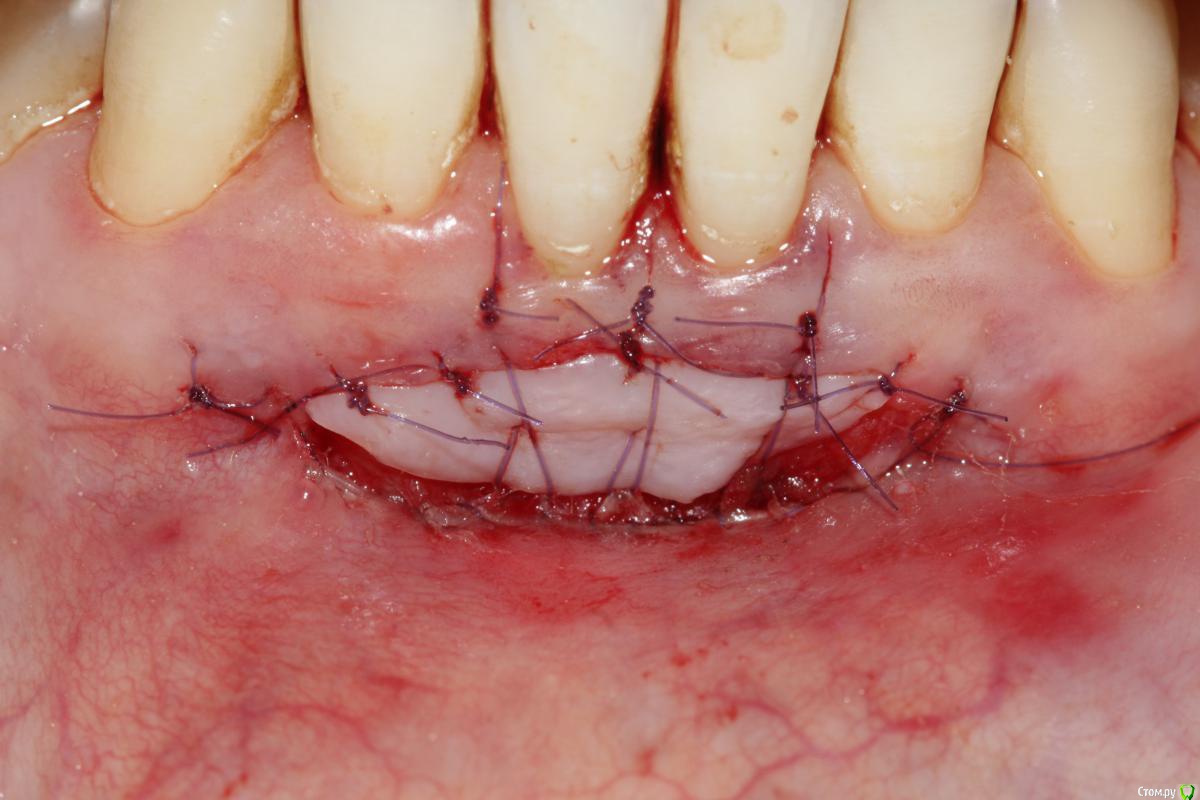

Dc.Petrov Опубликовано 11 февраля, 2015 Поделиться Опубликовано 11 февраля, 2015 Доброго дня! Подскажите, пжста, плюсы и минусы методики и прогноз конкретно приведенного случая Ссылка на комментарий

Dc.Petrov Опубликовано 11 февраля, 2015 Автор Поделиться Опубликовано 11 февраля, 2015 С какой целью вообще выполнена эта операция? увеличение ЗПКД, профилактика рецессии, при улыбке не видно Ссылка на комментарий

Dc.Petrov Опубликовано 11 февраля, 2015 Автор Поделиться Опубликовано 11 февраля, 2015 Минусы я полагаю Вы и сами видите. [/quote Вы имеете ввиду отличие по цвету? Ссылка на комментарий

Чертков Александр Опубликовано 11 февраля, 2015 Поделиться Опубликовано 11 февраля, 2015 (изменено) увеличение ЗПКД, профилактика рецессии, при улыбке не видноЕсть более "эстетичные" и менее инвазивные способы. Рецессии?...Где? Я бы такой уровень уздечки даже и не подумал как-то изменять. А если уж очень хочется, то можно было выполнить довольно простую френотомию(эктомию). Минусы я полагаю Вы и сами видите. [/quote Вы имеете ввиду отличие по цвету?Нет, цвет - дело второстепенное, а вот два грубых рубца получили...тем самым, действительно, поспособствовали возможности рецессии. Изменено 11 февраля, 2015 пользователем Чертков Александр Ссылка на комментарий